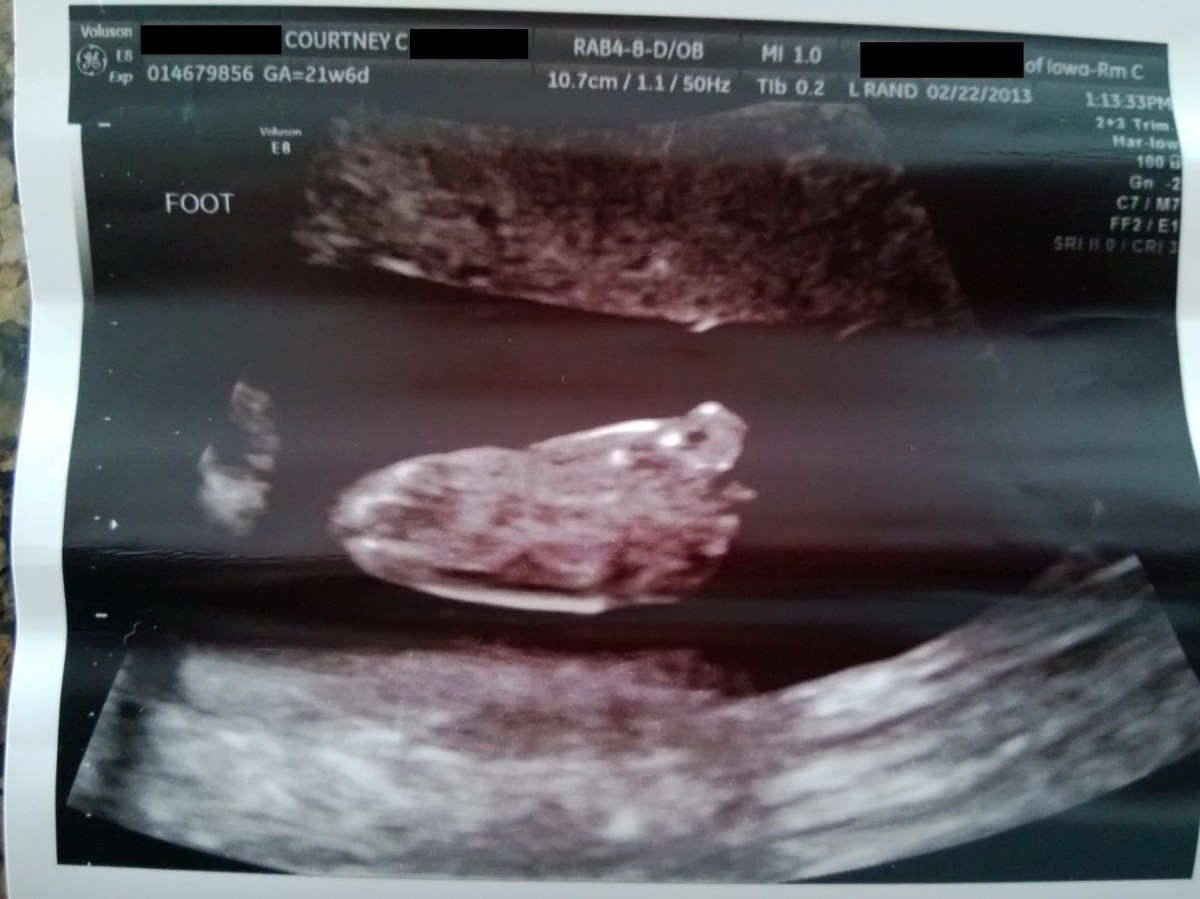

WP_20130222_008 February 22, 2013 by Courtney Leave a comment ← Previous Image Next Image → 21w6d – his second toe is longer than his big toe – just like mine! Like Loading...